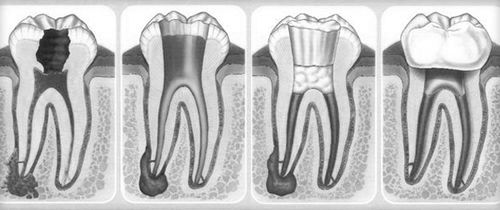

- періодонтит - формування абсцесу в зоні біля верхівки кореня зуба.

Як лікувати біль при періодонтит

Джерелом періодонтиту може бути як інфекційне зараження, так і травматичне вплив. На перших стадіях така проблема зазвичай себе не проявляє, поступово формується шишка на яснах - фіброзна капсула, яка з часом може перетворитися на кісту і заповнитися гноєм. Це дуже небезпечний стан, зване «бомбою уповільненої дії», адже при відсутності необхідного лікування при несприятливих умовах може розвинутися небезпечний процес, наприклад, сепсис.

З огляду на всю специфіку ситуації, зняття болю як симптому марно і небезпечно, так як проблема вимагає реального усунення причини. Так, лікар повинен видалити продукти запалення, забезпечити вихід гною з «шишки», запломбувати канал. Протягом 3-5 днів після такого лікування у пацієнта можуть виникати болінад зубом при натисканні. Тут вже доцільно скористатися знеболюючими таблетками.

Після пломбування зуба або установки коронки

В процесі установки пломби лікар виробляє такі маніпуляції: видаляє уражені зубні тканини, обробляє порожнину і поміщає в неї спеціальну прокладку, і після встановлює саму пломбу, підганяє її за розмірами і шліфує. Якщо карієс став причиною пульпіту, то необхідно видалення ураженої нерва. При установці коронки попередньо проводиться видалення нерва і пломбування каналу, що також має на увазі зачіпання живих тканин. Таким чином, зовсім не дивно, що після таких процедур пацієнта турбують болі.

Болі під коронкою або пломбою зазвичай носять ниючий характер і присутні кілька днів (при пломбуванні каналів неприємні відчуття можуть мати місце кілька тижнів). Якщо дискомфорт несильний, то лікарі радять його перетерпіти, якщо ж відчуття інтенсивні, то можна використовувати такі методи: